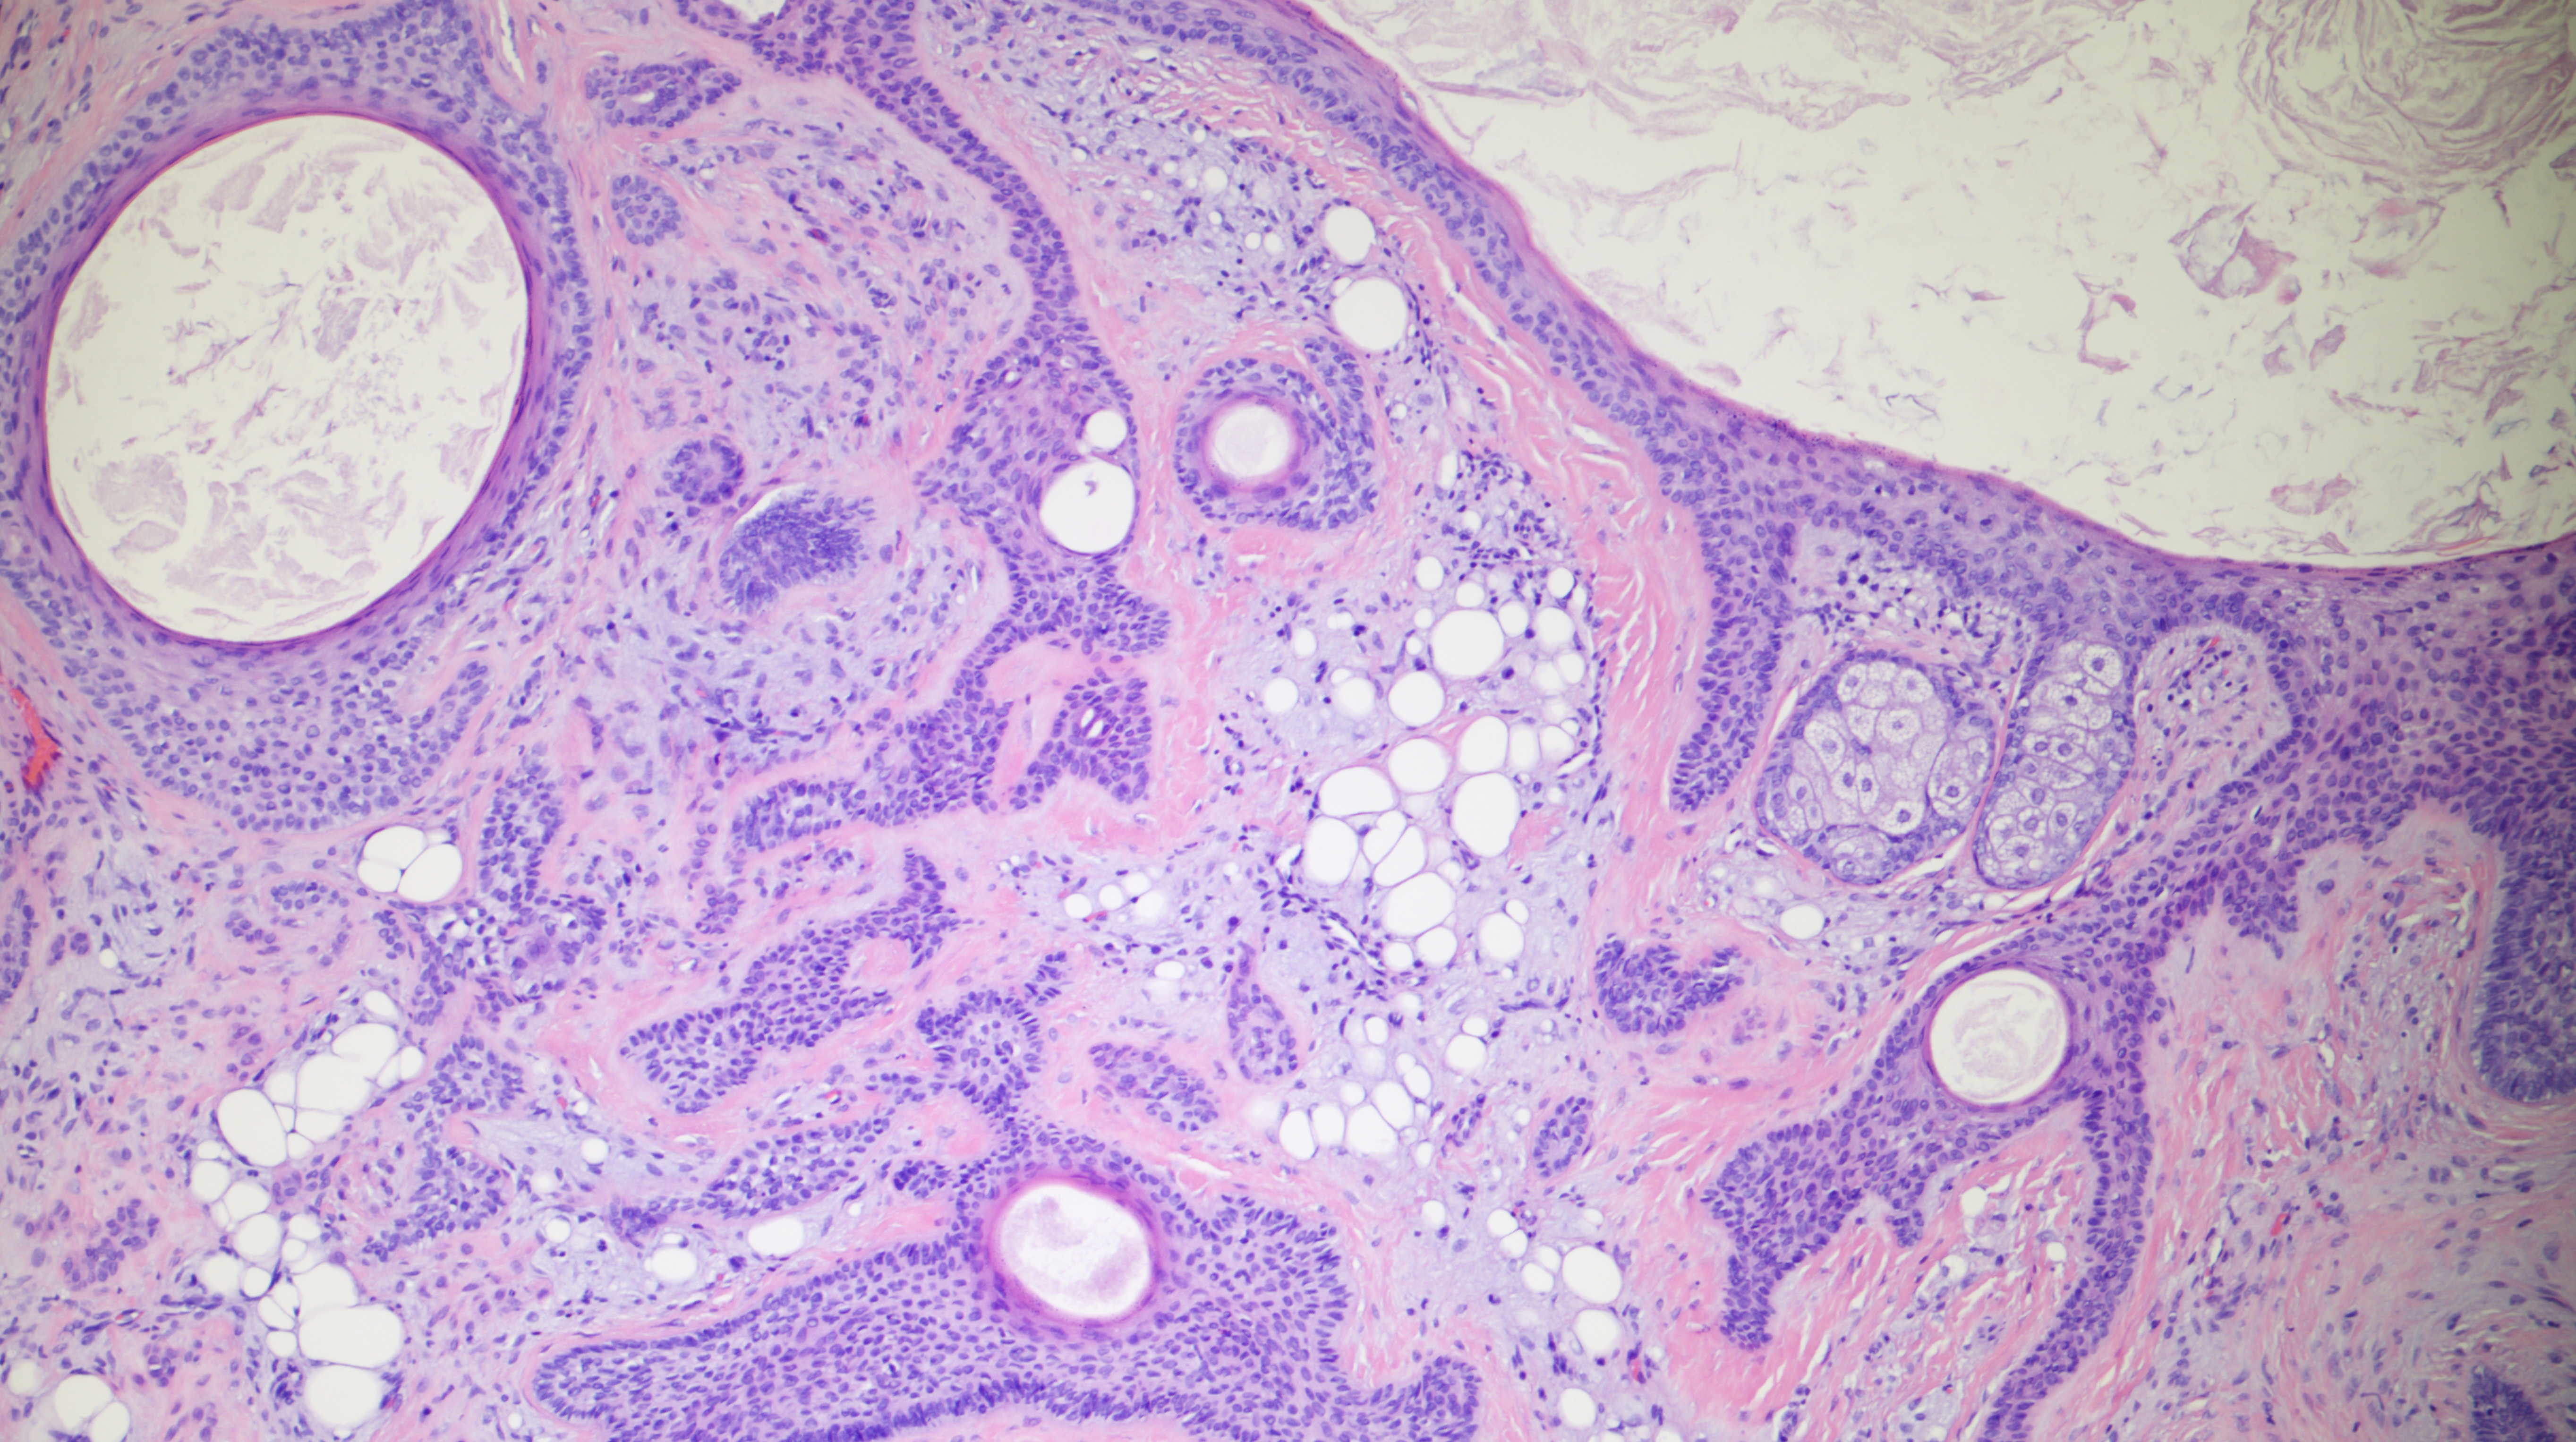

60-year-old man with an upper lip nodule.